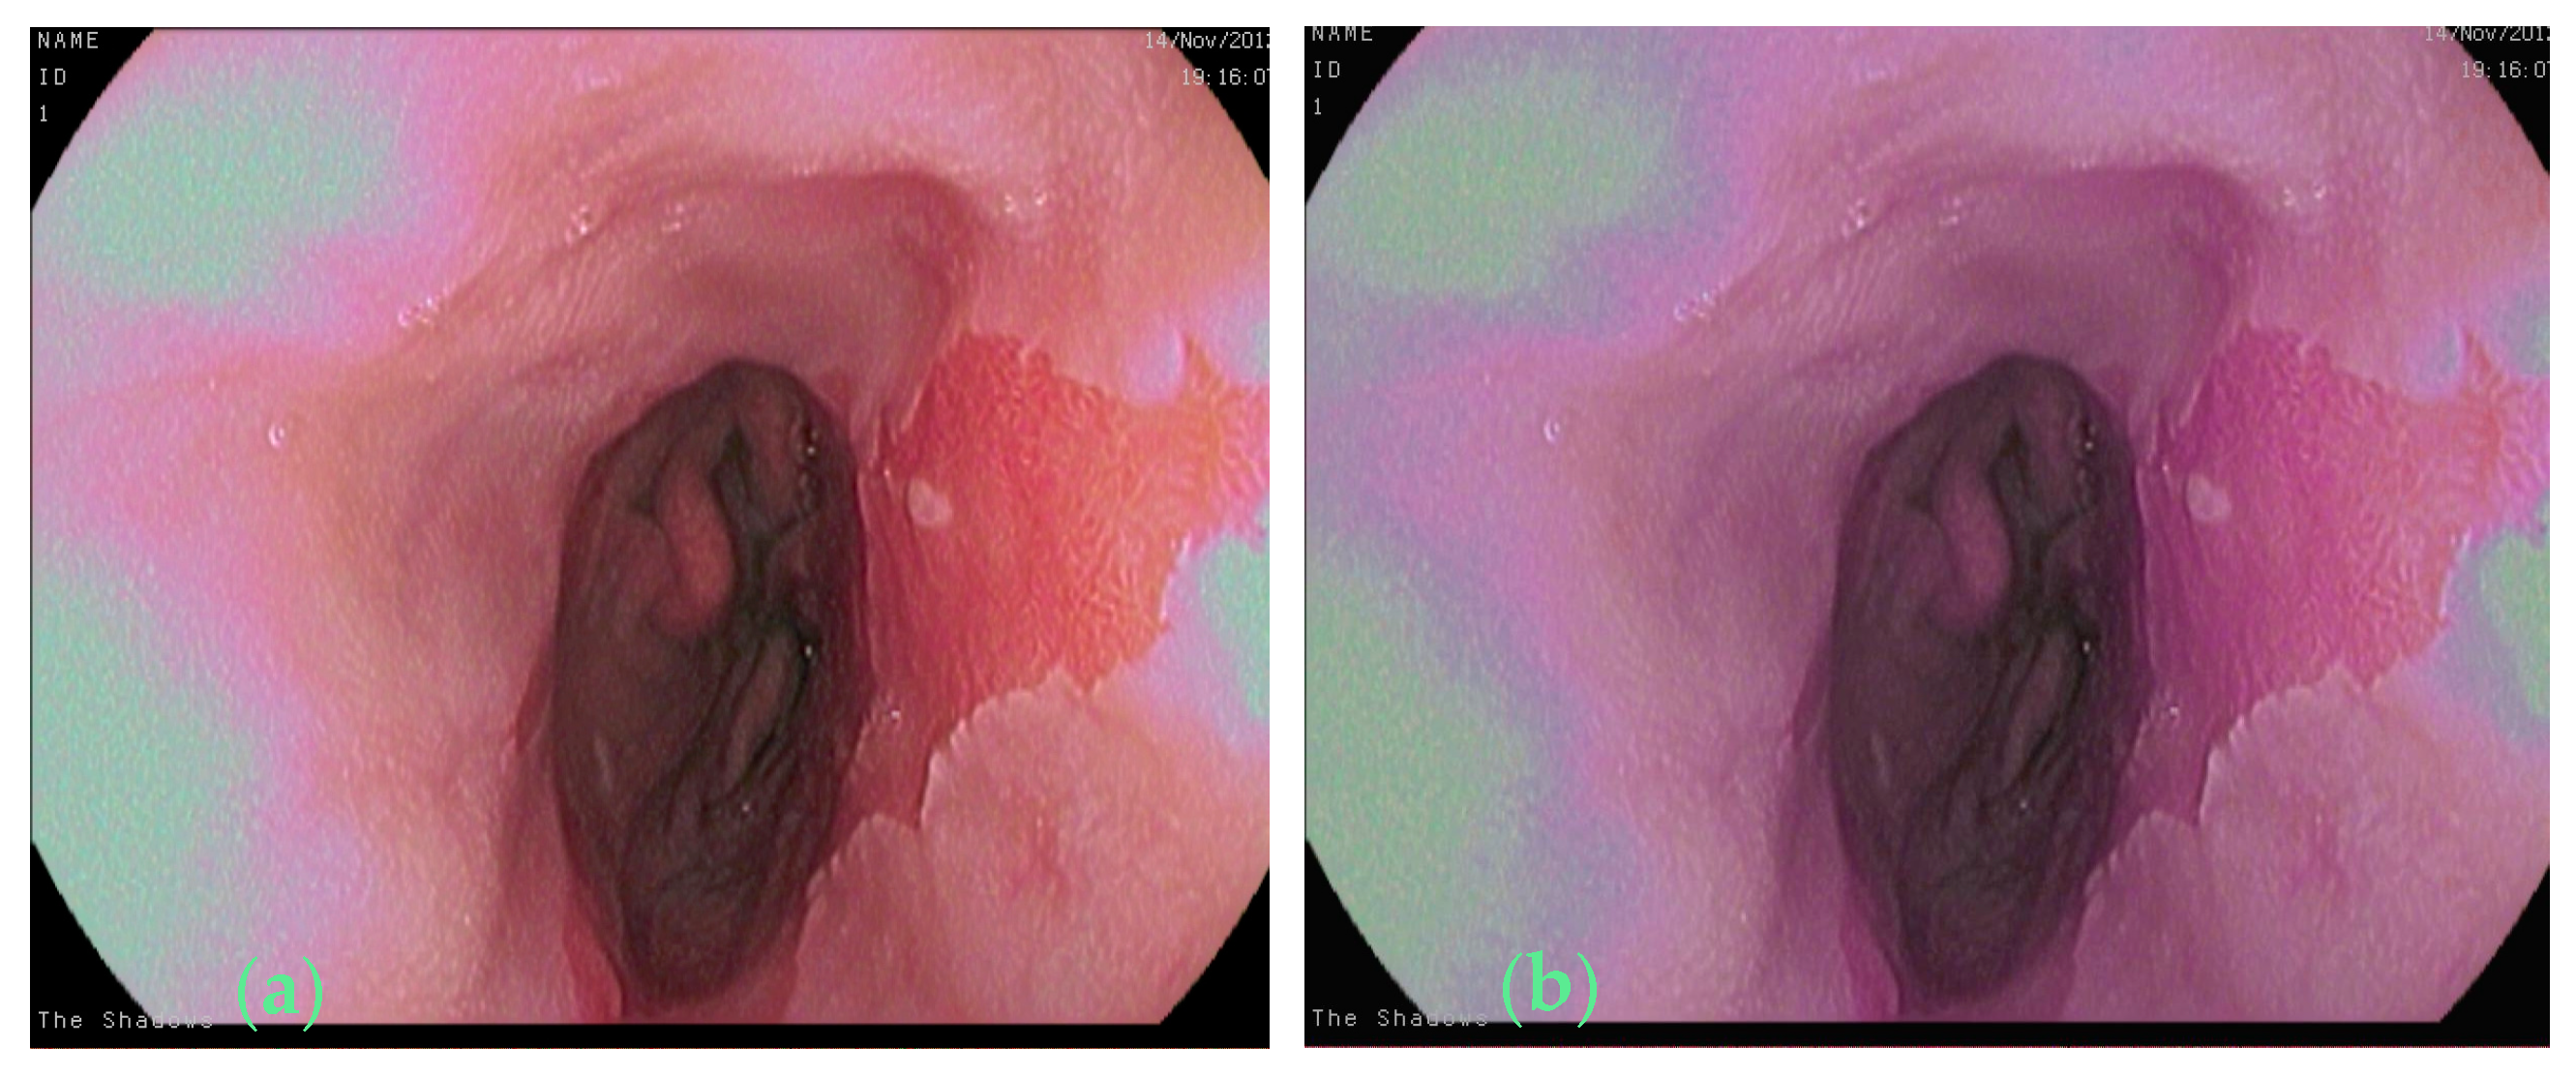

2.1. Raw Images and the Annotation Method